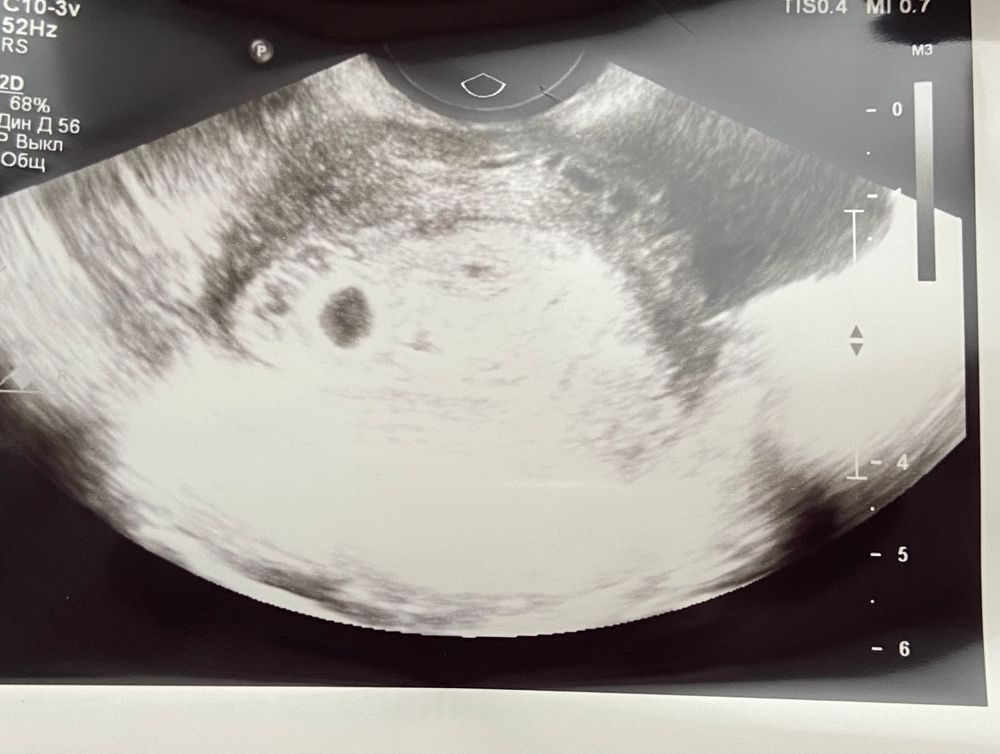

Желточный мешочек?!

Ульяна, здравствуйте, на каком размере ПЯ нашли желточный мешочек? Очень переживаю

РЕКА, здравствуйте, 16 мм, жт был 3мм

У меня так было, просто он еще крохотный, этот мешочек, не видно его

Просто маленькое еще все) у меня при ПЯ 14 мм, жм был 3

Всё хорошо))) через неделю будет жм, пока рано))) растите))